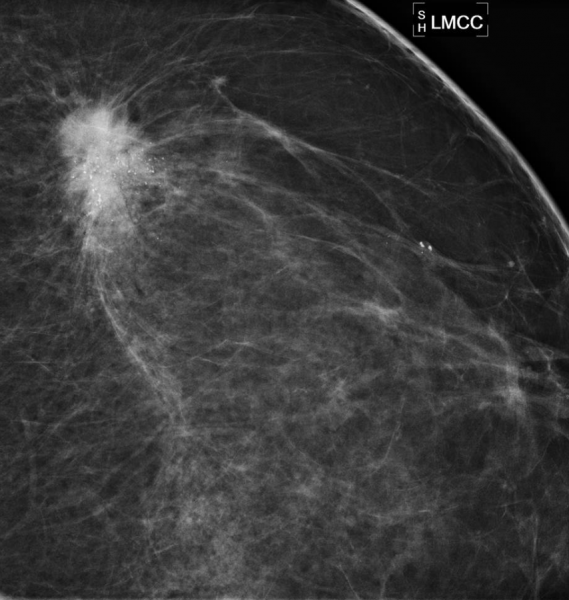

Patient 1: Bilateral MLO views from screening mammography in a 53-year-old woman.